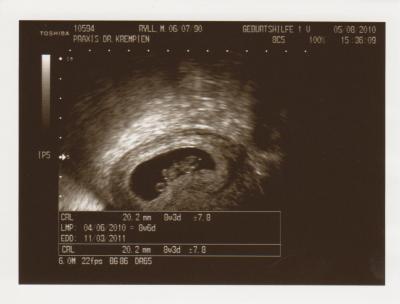

Das kleine Herzchen, wie es bubbert. Traumhaft

Es ist nun 2,2 cm groß.

und ein Bildchen habe ich natürlich auch bekommen

ET ist nun der 11.03.2011

Das Bild ist total schööööön! Da kann man das kleine Gummibärchen auch schon super erkennen...

Ach wie cool!! Du hast aber ein süßes Foto bekommen. Hat sichs ja ganz schön gemütlich gemacht, dein Krümel.